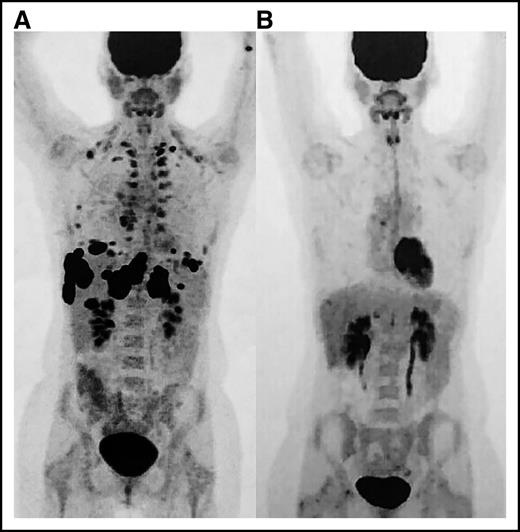

Positron emission tomography (PET) images. (A) Scan prior to initiation of nivolumab and (B) restaging PET after eighth cycle revealing complete remission.

Positron emission tomography (PET) images. (A) Scan prior to initiation of nivolumab and (B) restaging PET after eighth cycle revealing complete remission.

The patient’s ANC markedly improved within 3 days, but recovery was transient and required another dose of IVIG 11 days after the first dose (Figure 1). Computed tomography showed a pronounced partial response where no therapy had successfully worked before. It was for this reason that nivolumab was restarted in addition to rituximab to preemptively treat autoimmune neutropenia. The patient never again experienced neutropenia and ultimately developed a complete remission within 4 months (Figure 2). Now 18 months from remission, she has remained relapse free with normal blood cell counts at the time of this article’s submission.

A finding of equal importance in this report is the complete remission that occurred in this disease that was otherwise refractory to multiple lines of chemotherapy and radiotherapy. At the time of our decision to treat with nivolumab, there were no studies to show clinical efficacy nor was there evidence of PD-1–mediated immune escape in PMBCL. Nivolumab was pursued given the response appreciated in many of the patients in the phase 1 Hodgkin lymphoma trial2 and absence of other available treatment or active clinical trials. A recent study indeed showed that 36% of patients with PMBCL were positive for PD-L1 expression,10 which opened the feasibility of PD-1 blockade as a potential treatment of this disease. Another PD-1 antibody, pembrolizumab, was recently studied in a phase 1 trial of 18 patients with relapsed/refractory PMBCL, which reported an overall response rate of 41% and interestingly reported a single patient that developed neutropenia as well.11 Our patient’s clinical course supports that nivolumab could be an option for refractory PMBCL and warrants further investigation to potentially salvage the rare patients who fail traditional therapies.